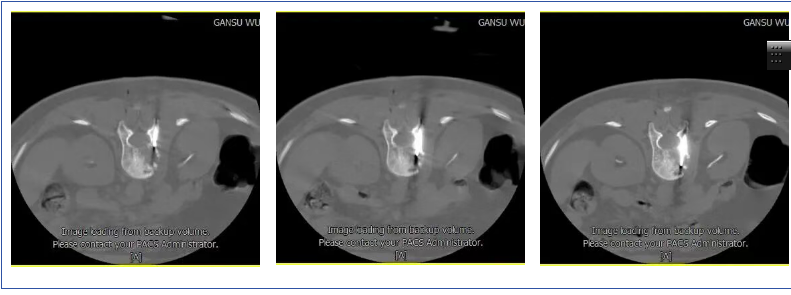

d:应用推杆少量多次注入骨水泥,观察病变区域骨水泥的填塞状况;

E:优骨水泥注射结束后,拔除穿刺针后再次扫描,确定骨水泥注射后情况。

3、骨水泥注入:穿刺完成后进行确认,所建立的工作通道完全位于脊柱椎骨的安全区域内,调配医用骨水泥(如聚甲基丙烯酸甲酯),应用导管或者注射器通过穿刺针缓慢注入椎体内,进行骨转移瘤的椎体强化,并通过骨水泥的产热作用行程局部的肿瘤杀伤作用。注射过程中反复进行影像复核,确保椎体后缘无骨水泥的渗漏。